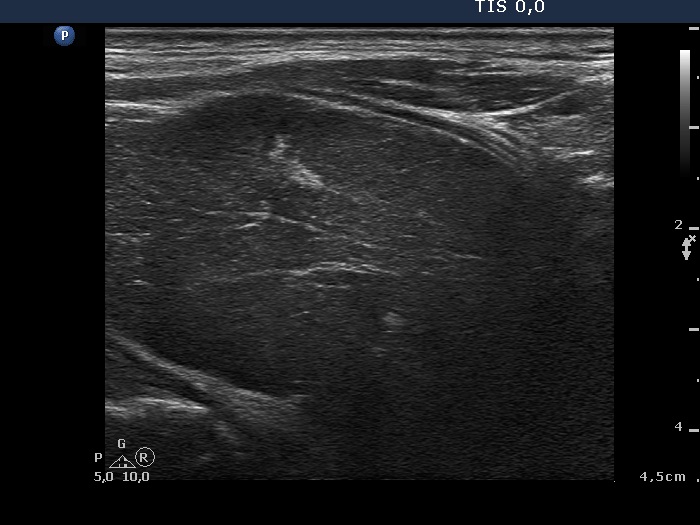

Ultrasonography. Both lobes were extremely enlarged, the dimensions of the right lobe was 75x55x120 mm. The whole thyroid was severely hypoechogenic, inhomogeneous. The vascularization was irregularly increased.